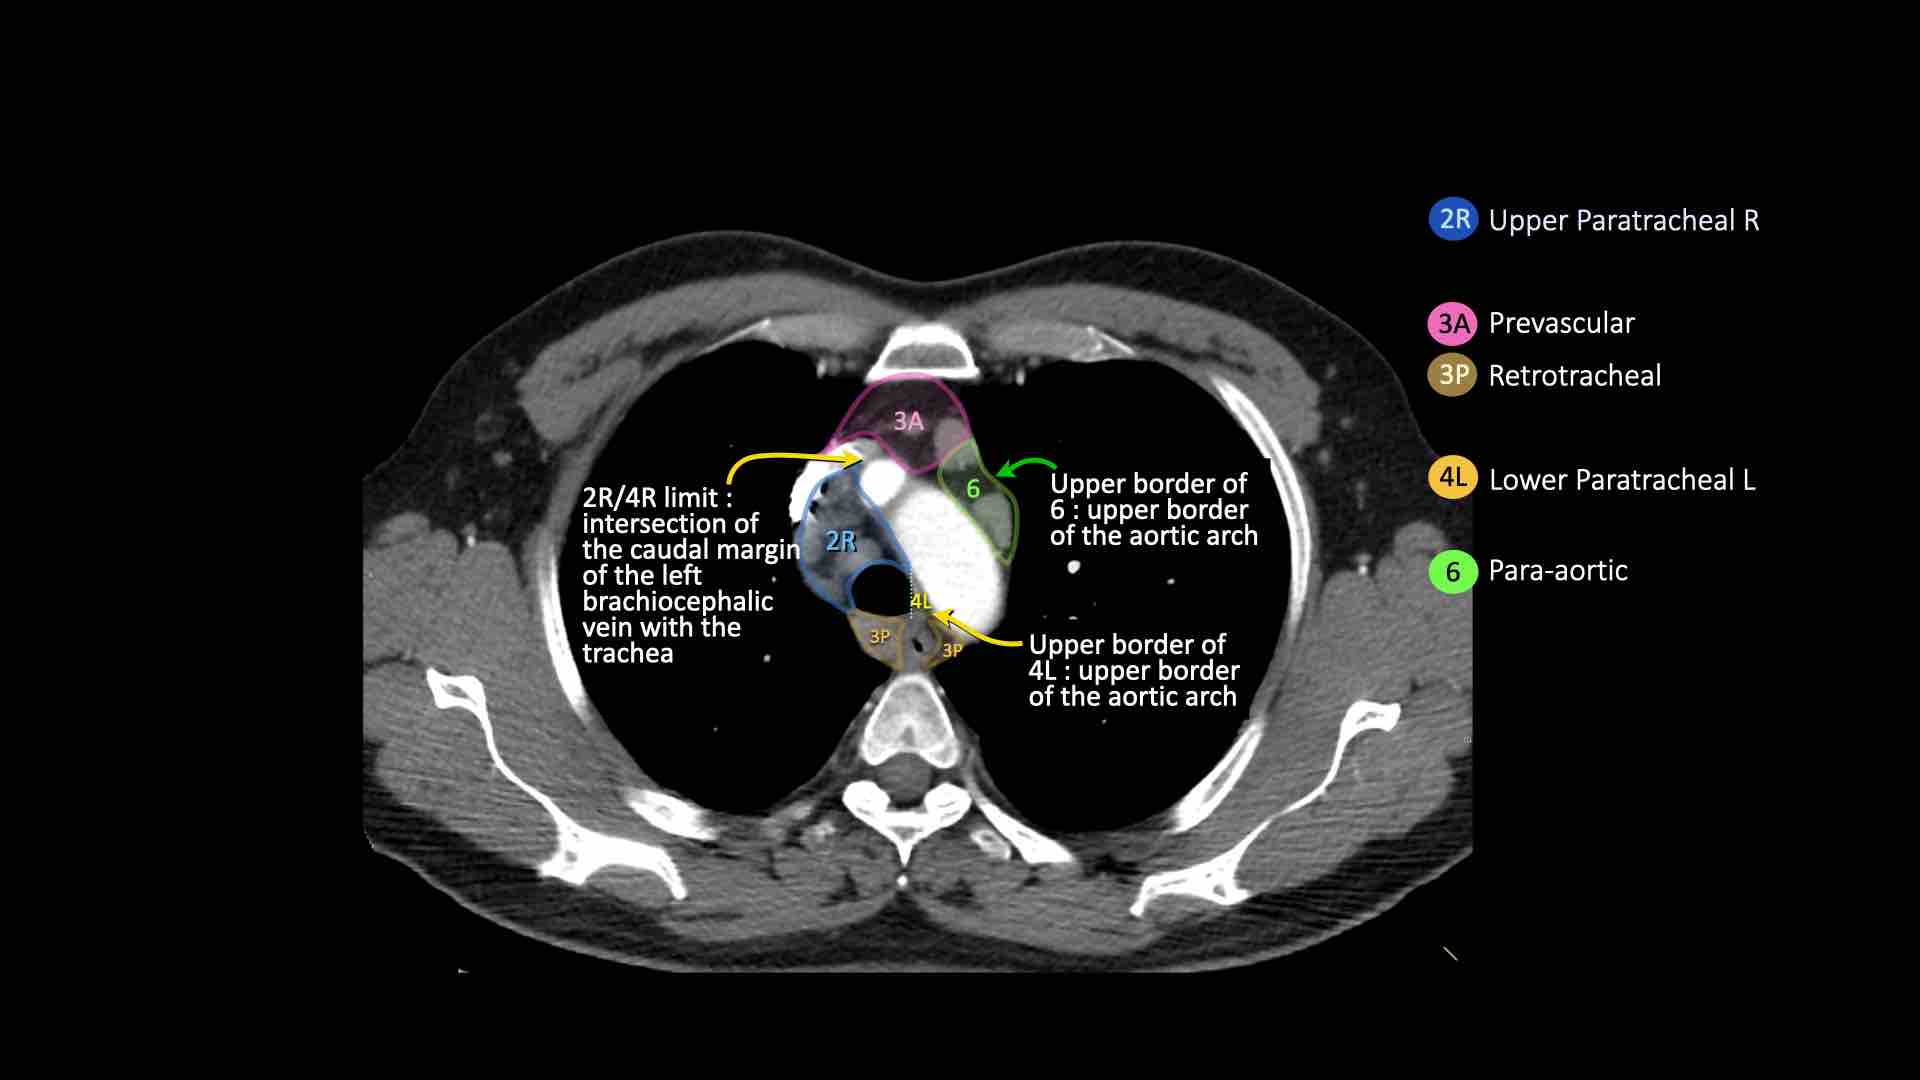

4R.Cạnh khí quản dưới

Từ điểm giao nhau giữa bờ dưới tĩnh mạch vô danh (tĩnh mạch tay đầu trái) với khí quản đến bờ dưới tĩnh mạch đơn.

Hạch nhóm 4R trải dài từ bờ bên phải đến bờ bên trái của khí quản.

4L.Cạnh khí quản dưới

Từ bờ trên của quai động mạch chủ đến bờ trên của động mạch phổi trái.

6. Cạnh động mạch chủ

Đây là các hạch của động mạch chủ lên hoặc hạch cơ hoành, nằm ở phía trước và bên của động mạch chủ lên và quai động mạch chủ.

4R. Hạch cạnh khí quản dưới bên phải

Ranh giới trên: giao điểm của bờ dưới tĩnh mạch vô danh (tĩnh mạch tay đầu trái) với khí quản.

Ranh giới dưới: bờ dưới tĩnh mạch đơn.

Hạch nhóm 4R trải dài đến bờ bên trái của khí quản.

Bên trái là hạch cạnh khí quản 4R.

Ngoài ra còn có một hạch động mạch chủ nằm bên ngoài quai động mạch chủ, tức là hạch nhóm 6.

4L. Hạch cạnh khí quản dưới bên trái

Hạch nhóm 4L là các hạch cạnh khí quản dưới nằm bên trái bờ trái của khí quản, giữa đường nằm ngang tiếp tuyến với bờ trên quai động mạch chủ và đường tiếp tuyến với bờ trên động mạch phổi trái.

Nhóm này bao gồm các hạch cạnh khí quản nằm ở phía trong dây chằng động mạch.

Hạch nhóm 5 (cửa sổ phế động mạch) nằm ở phía ngoài dây chằng động mạch.

6. Hạch cạnh động mạch chủ

Hạch cạnh động mạch chủ (động mạch chủ lên hoặc cơ hoành) nằm ở phía trước và bên ngoài động mạch chủ lên và quai động mạch chủ, từ bờ trên đến bờ dưới của quai động mạch chủ.

- Cạnh khí quản dưới: từ bờ trên cung động mạch chủ xuống đến mức phế quản gốc

- Dưới động mạch chủ (cửa sổ A-P): các hạch bạch huyết nằm bên ngoài dây chằng động mạch hoặc bên ngoài động mạch chủ hay động mạch phổi trái

- Cạnh động mạch chủ: các hạch bạch huyết nằm ở phía trước và bên ngoài động mạch chủ lên và cung động mạch chủ, bên dưới bờ trên của cung động mạch chủ